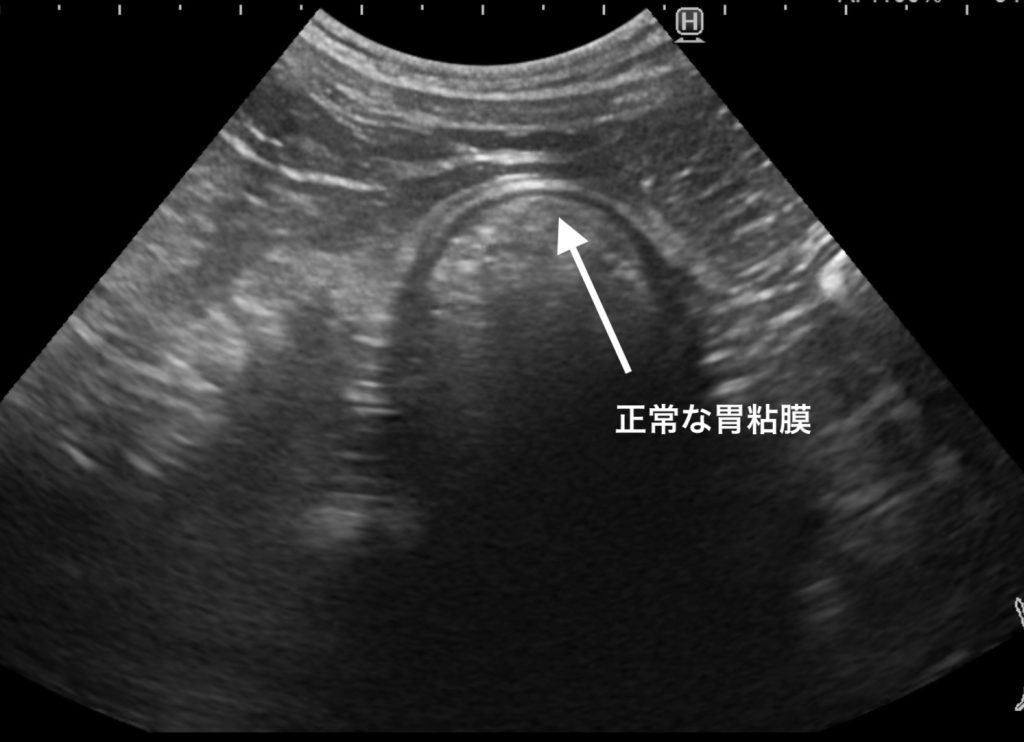

正常な胃粘膜については、薄く線状に見えることが基本になります。